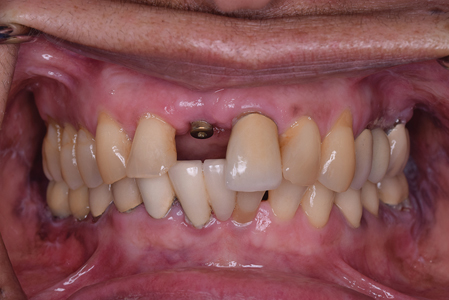

Minimally Invasive, Inter-Disciplinary Management for Cosmetic Rehabilitation in a High Smile Line Patient: A Case Report

Said-Picture6 alternate text for this image

Introduction: The purpose of this case report is to illustrate the potential of utilizing digital technology to minimize surgical invasion and increase precision in management of compromised sites in the esthetic zone. Article In modern-day implant dentistry, the ability to achieve a harmonious integration of the implant restoration is no longer optional but to a … Read more